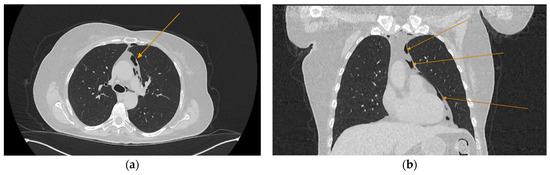

Given the patient’s history of vomiting, and consulting with the thoracic surgeon, a second CT scan with oral contrast was performed approximately 3 h later, after initial stabilization of the patient, to rule out an esophageal rupture. The subsequent imaging revealed the progression of the pneumomediastinum, with increased extension into the cervical region, including the peritracheoesophageal, perithyroidal and retropharyngeal spaces (Figure 3), without evidence of esophageal rupture (Figure 4). Oxygen therapy and empiric antibiotic therapy were initiated in the ED as initial treatments of this condition.

Figure 3.

Repeated chest and neck CT scans showcasing extension of the pneumomediastinum (arrows), axial views: (a) air tracking into the cervical soft tissues and prevertebral space; (b) air around airway structures; (c) pneumomediastinum surrounding the trachea.